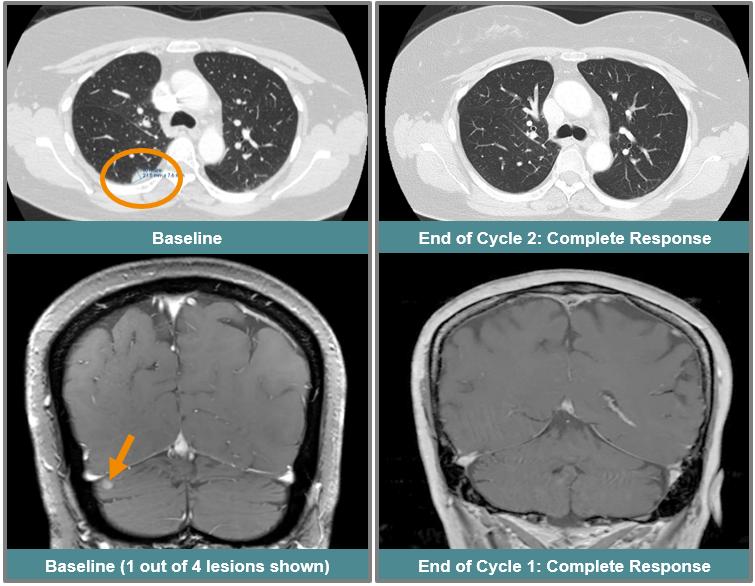

This patient, a 55-year-old woman with EGFR exon 20 mutated NSCLC previously treated and progressed on platinum-based chemotherapy followed by amivantamab, had four active CNS non-target lesions at study entry that had not been previously treated with either surgery or radiation. The patient received 75 mg once daily of ORIC-114, and by the end of the first cycle had a 60% reduction in all systemic target lesions, which improved to a complete response at the next cycle, with 100% reduction of all target lesions and disappearance of non-target lesions. The complete response was subsequently confirmed. The patient also had a complete response of all CNS disease after the first cycle with complete resolution of all four CNS lesions, which was also confirmed at a later scan.

Confirmed intracranial and systemic response in a patient with EGFR exon 20 mutated NSCLC and active CNS metastases that progressed on prior EGFR exon 20 targeted therapy.

http://api.rkd.refinitiv.com/api/FilingsRetrieval3/.77711830.0000950170-24-029298img260370254_16.jpg.ashx